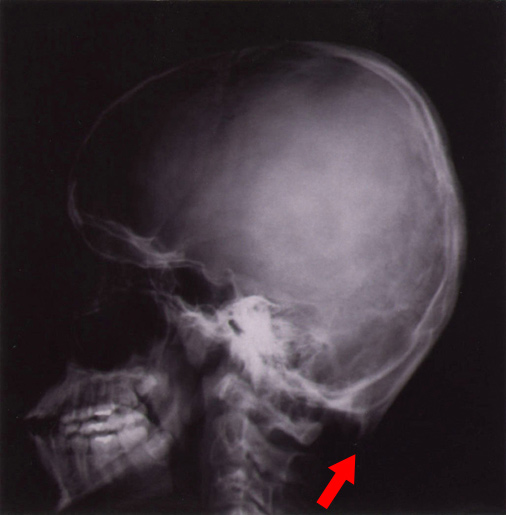

- 後頭骨に角様変化が見られるのが特徴である。血液検査では血清セルロプラスミン、銅は正常~低値。培養皮膚線維芽細胞の銅濃度高値

| 後頭骨の角様変化 | |